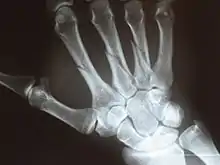

X-ray

Fracture

The neck of a metacarpal is a common location for a boxer's fracture, but all parts of the metacarpal bone (including head, body and base) are susceptible to fracture. During their lifetime, 2.5% of individuals will experience at least one metacarpal fracture. Bennett's fracture (base of the thumb) is the most common.[4] Several types of treatment exist ranging from non-operative techniques, with or without immobilization, to operative techniques using closed or open reduction and internal fixation (ORIF). Generally, most fractures showing little or no displacement can be treated successfully without surgery.[5] Intraarticular fracture-dislocations of the metacarpal head or base may require surgical fixation, as fragment displacement affecting the joint surface is rarely tolerated well.[5]

X-ray image of right hand with thumb on left.

Multiple fractures of the metacarpals (aka broken hand). (Right hand shown with thumb on left.)